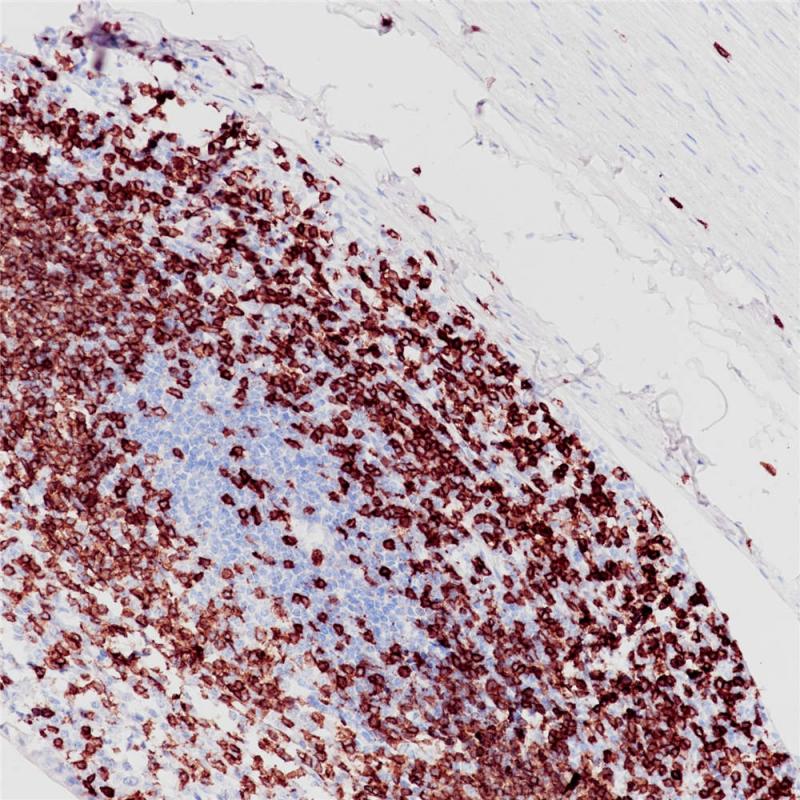

CD3 重组兔单克隆抗体

阳性对照

扁桃体